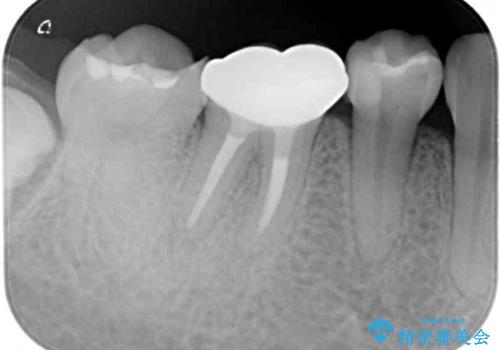

当院にて根管治療を行った後に、フルジルコニアクラウンにて補綴することとしました。

前医での根管治療の度に感じていた痛みの原因は分かりませんでしたが、元々違和感すらなかった歯であったので、速やかに根管治療を行った後に、ジルコニアクラウンを装着しました。

咬み合わせが強く、歯の高さが非常に低かったため、審美性には劣るものの、高強度であるフルジルコニアクラウンを採用しました。